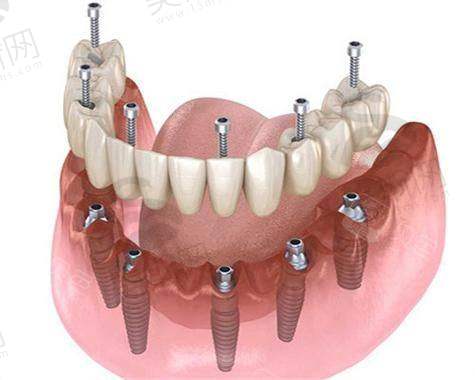

长春345口腔医院作为吉林国健医疗集团旗下的连锁牙科品牌,以“种植牙工厂店”为特色,4家连锁分院正规靠谱,在种植牙方面口碑良好。下面从技术与服务亮点来详细了解一下:

- 作为总院,设备齐全。在种植牙领域,擅长数字化导板种植,这种技术可以精细定位种植位置,提高种植的成功几率和正确性。对于中老年半口/全口修复也有丰富的经验,能够根据患者的具体情况制定个性化的修复方案。

- 是家庭友好型院区,设有儿童独立游乐区,让带孩子来看牙的家长更加放心。在种植方面,主打舒适微创种植,减少患者在种植过程中的痛苦。全口吸附性义齿修复技术也较为成熟,能够为患者提供舒适、稳定的义齿修复成效。

- 各分院能够开展多种精良的口腔技术,如数字化导板种植、即刻种植、骨量不足种植、青少年隐形矫正、舒适微创种植、全口吸附性义齿修复等,这些技术的开展需要医生具备扎实的专精知识和丰富的临床经验。例如,数字化导板种植需要医生熟练掌握口腔CT数据的分析和导板的设计与应用;即刻种植技术要求医生在短时间内完成种植手术,并且确保种植体的稳定性和初期愈合成效。